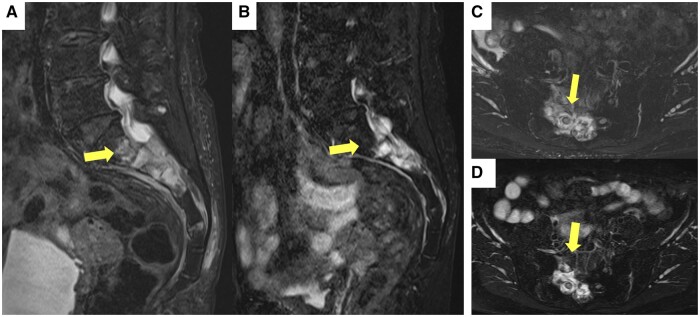

Methotrexate (MTX) is a drug used for treating rheumatoid arthritis. Recently, the reported incidence of methotrexate-associated lymphoproliferative disease (MTX-LPD) has increased, especially in Japan. Extranodal involvement is observed in half of MTX-LPD cases. However, only a few spinal lesions have been reported, with none in the sacrum. Additionally, Epstein-Barr virus (EBV) infection has also been implicated in the pathogenesis of MTX-LPD. Herein, we describe the case of a 74-year-old woman with MTX-LPD in the sacral spine who complained of severe back pain and nocturnal pain. Radiographs revealed a tumour on the right wing of the sacrum and a positive EBV immunoglobulin G antibody titre. MTX-LPD was suspected based on imaging findings and a history of MTX administration. A pathological examination was performed on the CT-guided biopsy specimen. The histopathological diagnosis was MTX-LPD, and MTX was discontinued. Three months after MTX administration ended, the tumour tended to shrink, and 1 year later, significant tumour shrinkage was observed. This experience suggests that MTX-LPD can be treated by discontinuing MTX administration. Therefore, early and accurate diagnosis is required, as is avoiding unnecessary treatment such as surgery. MTX-LPD should be considered, especially in spinal origin tumours in EBV-infected patients on MTX.